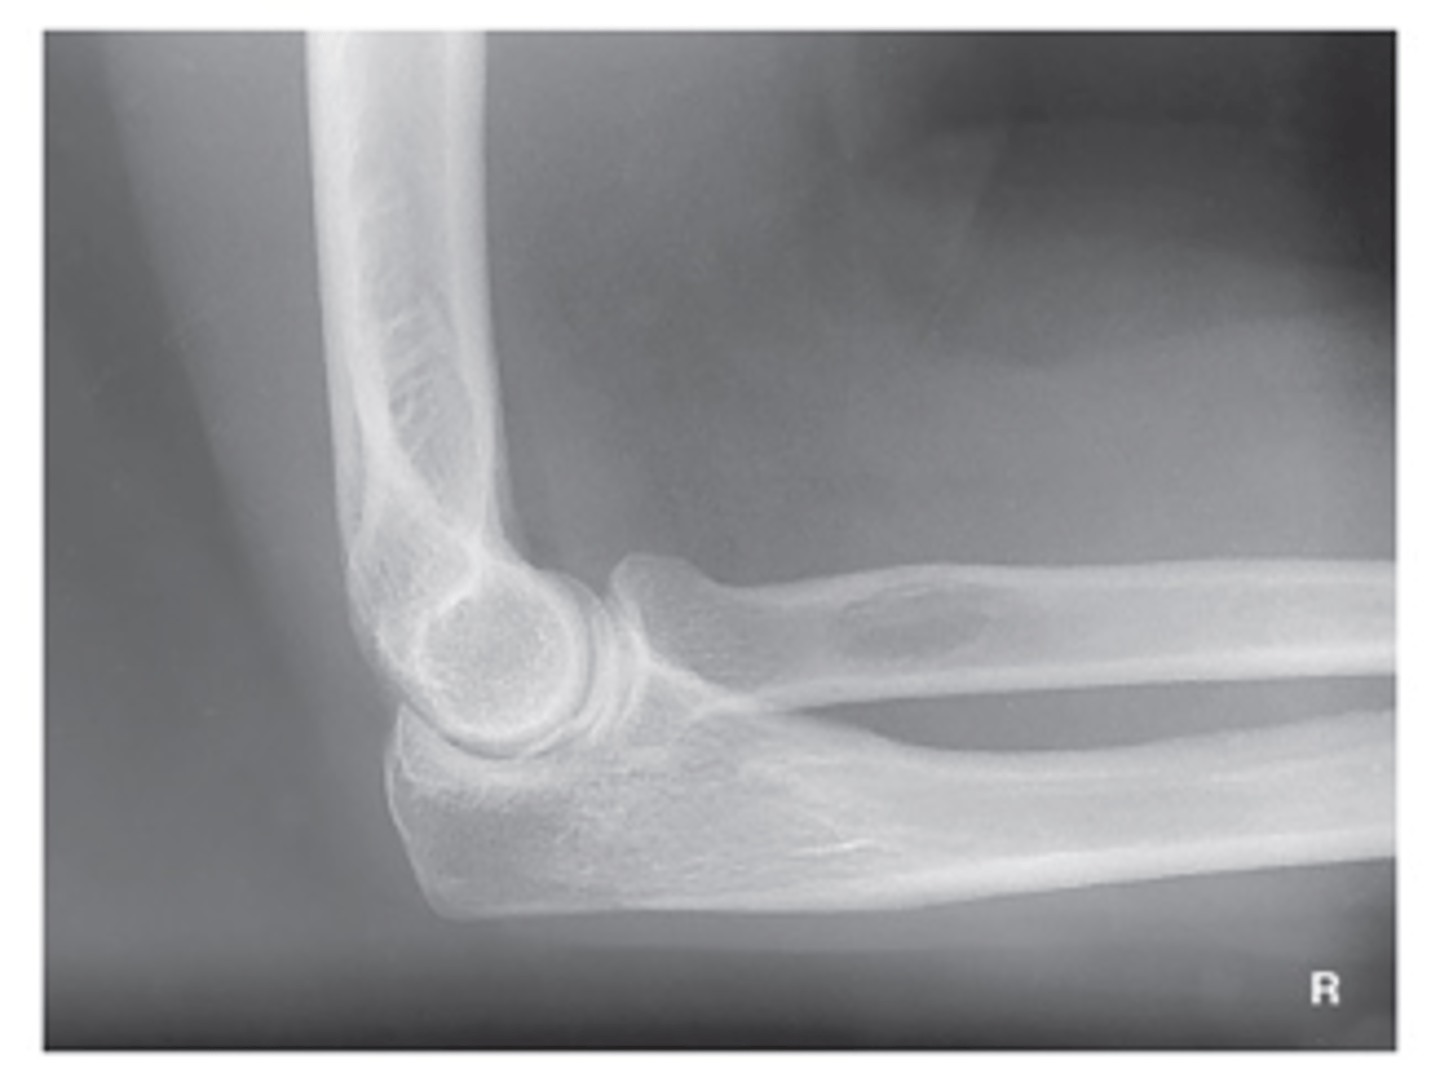

Lateral Elbow

Axial lateromedial for radial head elbow